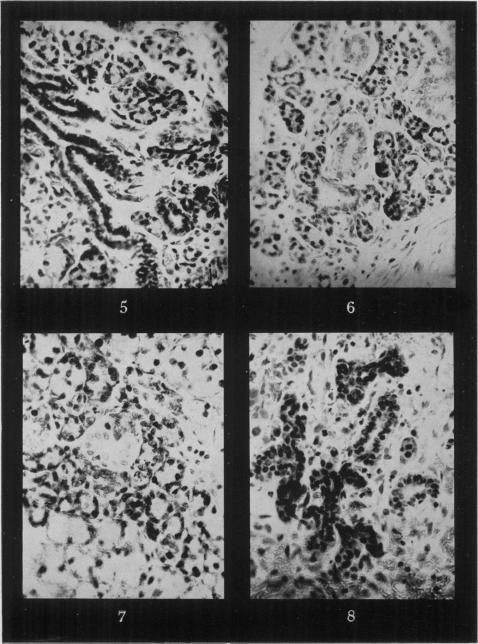

Regeneration in the submaxillary gland of the rat.

Br J Exp Pathol. 1950 Oct;31(5):664-9.